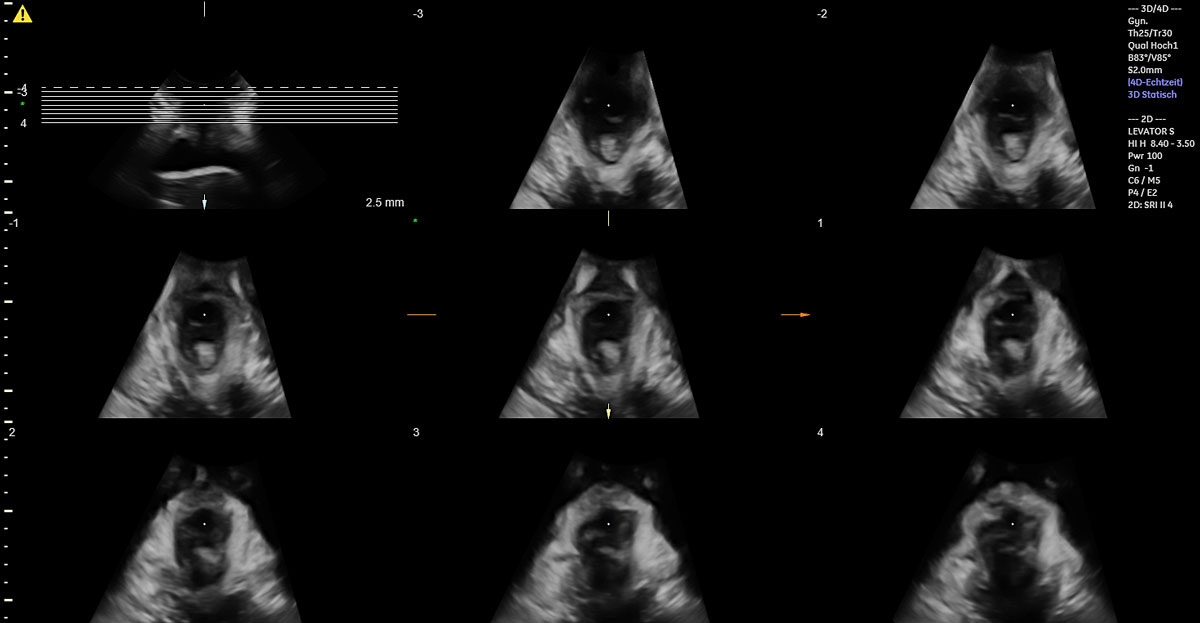

Of the 49 women with vacuum-assisted births in our cohort, 32 (65.3%) had an intact levator ani muscle, as shown in the illustration in fig. 2a and in the 3D ultrasound scan in fig. 2b. In contrast, 17 (34.7%) sustained levator ani muscle trauma, with 9 women (18.4%) having a partial levator ani muscle avulsion and 8 women (16.3%) having a complete levator ani muscle avulsion, as shown in the illustration in fig. 3a and in the 3D ultrasound scan in fig. 3b. No significant differences between the two groups were found, except for the state of their uterine contractions. Women without any levator ani muscle injury after vacuum extraction had more efficient uterine contractions compared to women with levator ani muscle trauma.

Figure 2a Illustration of an intact bilateral levator ani muscle.

Figure 2b 3D translabial ultrasound image of an intact bilateral levator ani muscle.